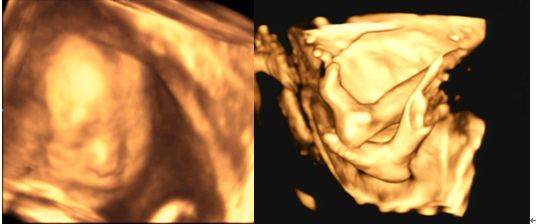

④工作中,突然看见胎儿对我欢笑,对我说悄悄话。⑤值班时,与病号度过的每一个日日夜夜,看到患者康复的笑容。⑥看见年轻医师快速成长,科室和谐进步,朝气蓬勃!